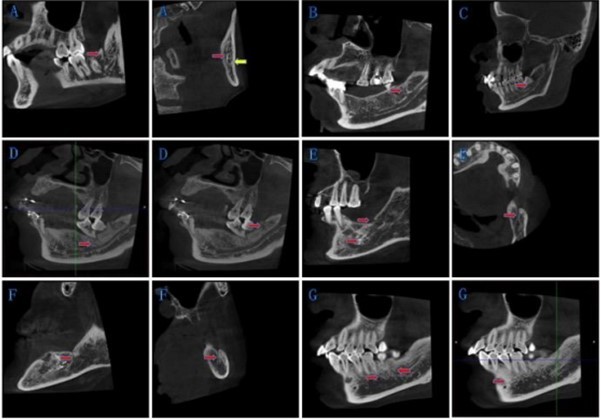

Table 1. New classification of bifurcated mandibular canal| I | IA | A bifurcation at the mandibular ramus and the retromolar foramen has been formed. (Fig. 2A,B; Note 1) |

| IB | A bifurcation at the mandibular ramus and the retromolar foramen has not been formed. (Fig. 2C) | |

| II | Bifurcations at the mandibular body. (Fig. 2D) | |

| III | Bifurcations exist both at the mandibular body and the mandibular ramus on one side. (Fig. 2E; Note 2) | |

| IV | Other circumstances (e.g., trigeminal nerve canal or multi-canal derived from different origins) (Fig. 2F) | |

According to our rules, we divided BMC into four types. Type IA was bifurcations at the mandibular ramus, and retromolar foramen has been formed. Type IB was bifurcations at the mandibular ramus, and retromolar foramen has not been formed. We took those bifurcations at mandibular body as Type II. Type III was for bifurcations exist both at the mandibular body and the mandibular ramus on one side. Type IV for other circumstances. Details as following in Table 1 and Figure 2

*Note 1: If there are several branches at one side of the mandibular ramus at the same time,we add total numbers before the type and specific amount of subclass on the bottom right (e.g., 2IA, 3IA2B1). If the bifurcation point is exactly on the boundary of the body and ramus, we identify it as Type I.

*Note 2: If there are several branches, the number before the type represents the total amount, and the label at the top right shows the number of branches at the mandibular ramus; the label at the bottom right shows the number of branches at the mandibular body

Figure 2.New classification of BMC: The red arrow points to the bifurcations, and the yellow arrow points to the mandibular canal. (A) Type IA: Bifurcations at the mandibular ramus, and retromolar foramen has been formed. (B) Type IB: Bifurcations at the mandibular ramus, and retromolar foramen has not been formed. (C) Type II: Bifurcations at the mandibular body. (D)-(F) Type III: Bifurcations exist both at the mandibular body and the mandibular ramus on one side. (G) Type IV: Other circumstances.